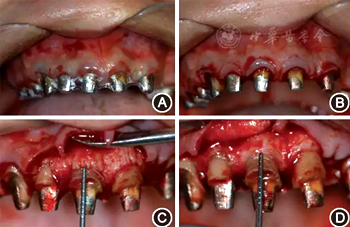

(2)手術(shù)導(dǎo)板指導(dǎo)下的牙冠延長術(shù):根據(jù)最終診斷蠟型,制作透明墊式手術(shù)導(dǎo)板(圖4B),指導(dǎo)上頜牙冠延長術(shù)(圖5),最終達(dá)到改善牙齦形、線、點的美學(xué)要求,獲得協(xié)調(diào)、對稱的美學(xué)效果。

圖5 有利于健康、功能及美學(xué)效果的牙冠延長術(shù)手術(shù)過程 A:戴入手術(shù)導(dǎo)板;B:在手術(shù)導(dǎo)板的指導(dǎo)下確定手術(shù)切口;C:翻瓣后可見唇側(cè)骨板肥厚、形態(tài)不佳,上前牙鄰面及唇側(cè)原有肩臺距離骨嵴頂≤ 2 mm,侵犯了生物學(xué)寬度;D:骨切除及骨成形后唇側(cè)骨板形態(tài),肩臺距牙槽嵴頂約4 mm;E:齦瓣復(fù)位縫合,原有肩臺均位于齦上